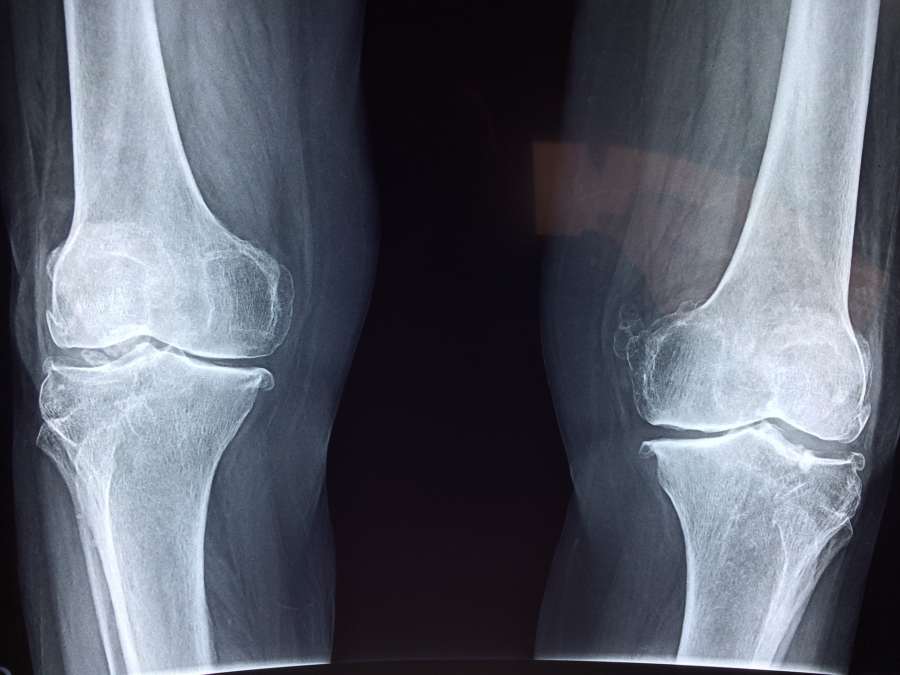

Za bolestí kloubů může stát hned několik příčin. Zajímá vás, jaké to jsou? Jak si můžete od bolesti ulevit sami? A jak vám s bolestí kloubů pomůžeme my?

Bolest kloubů může být způsobena napadením těla vnějšími škodlivinami. A to nejčastěji vlhkem a chladem. K tomu může dojít zejména, pokud je obranná čchi těla slabá a škodliviny do těla propustí. Nebo příliš dlouhým pobytem v chladnu a vlhku.

Stálým pnutím v kloubech vzniká horko, které se tělo snaží vyrovnat tekutinou. Vznikají tak otoky kloubů, nebo voda v koleni. V první fázi pomůžou baňky a akupunktura. Tím se ovšem řeší jen následek. Proto je třeba se zastavit, případně se “resetovat”, začít vnímat co mám v sobě a nějak se k tomu postavit. Tady velmi pomáhá jóga a čchi-kung.

V místě, kde stagnuje energie, přestává téct i lymfa. Okolí kloubu plné staré a tuhé lymfy potom neumožňuje dostatečné čištění, obnovu a výživu kloubu. A kloub může začít skutečně degenerovat.